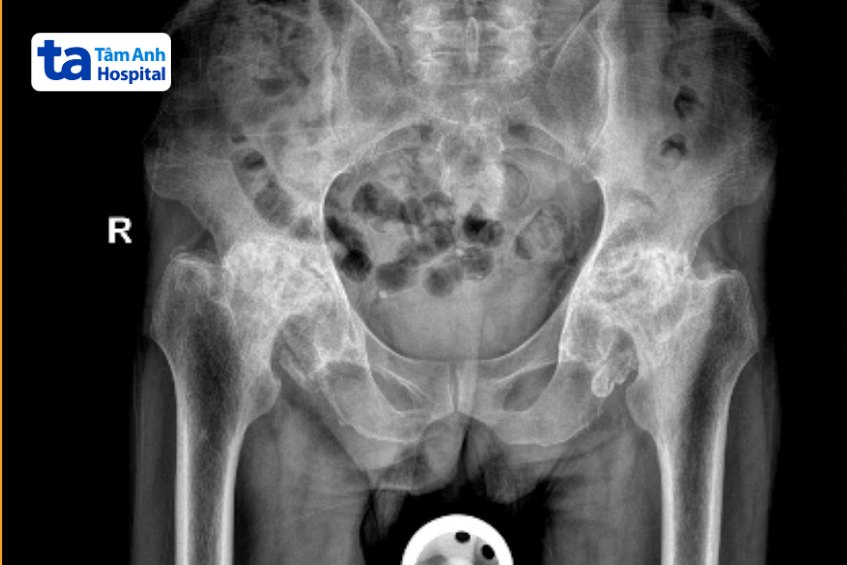

ThS.BS.CKI Nguyễn Văn Lưu, Trung tâm Chấn thương Chỉnh hình, Bệnh viện Đa khoa Tâm Anh TP HCM, cho biết kết quả chụp X-quang cho thấy tình trạng hoại tử chỏm xương đùi của ông Nhựt đã phát triển đến giai đoạn cuối ở cả hai chân, thoái hóa và xuất hiện nhiều gai xương.

“Người bệnh cố vận động trong thời gian dài với tình trạng chỏm xương đùi biến dạng, có gai xương nên ổ cối bị khoét rộng rất lớn”, bác sĩ Lưu nói, thêm ràng hiện ông Nhựt còn có nhiều vấn đề về sức khỏe như suy tuyến thượng thận (cushing), loãng xương, đái tháo đường, rối loạn đường huyết và chuyển hóa, mỏng da, teo cơ, vết thương khó lành… Tất cả là do hậu quả của việc tự ý dùng thuốc giảm đau chứa corticoid trong thời gian dài.